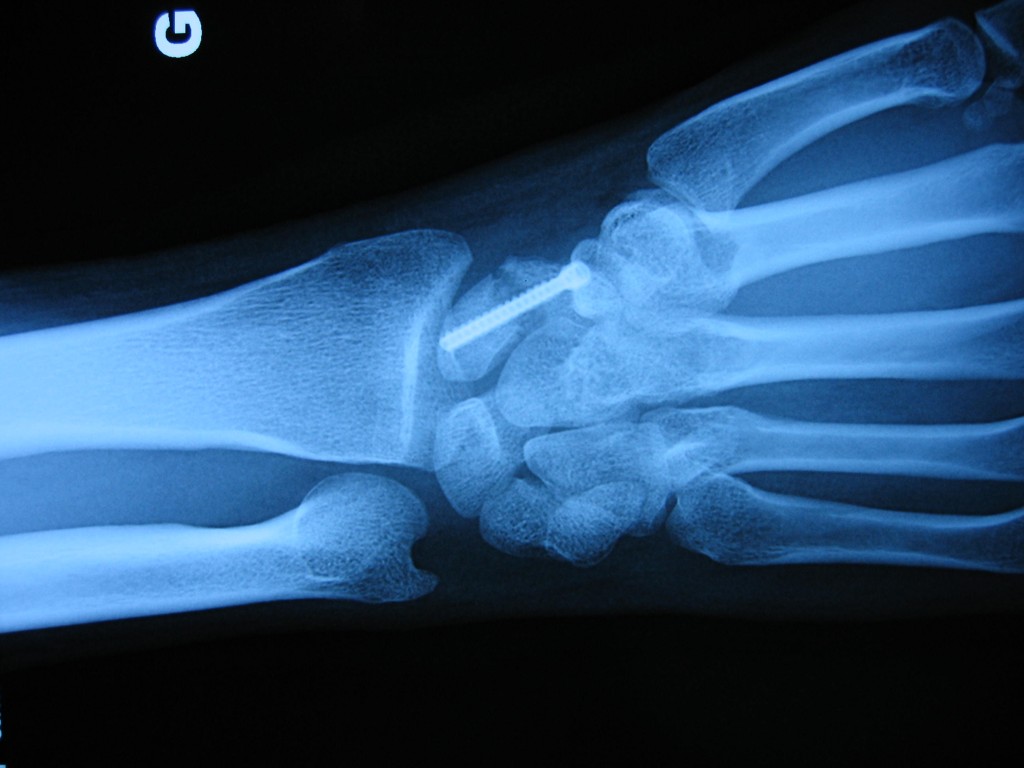

Open Reduction and Internal Fixation of Scaphoid Fractures Sport Scaphoid Fracture The goal in treatment of scaphoid fractures in the elite athlete is to expedite healing so that the athlete may return to sport. Surgical treatment of scaphoid fractures requires careful evaluation of each specific fracture pattern, and treatment must be individualized for each athlete. Stress on the scaphoid, due to a forceful motion, may have a fracture as result (mostly. Sport Scaphoid Fracture.